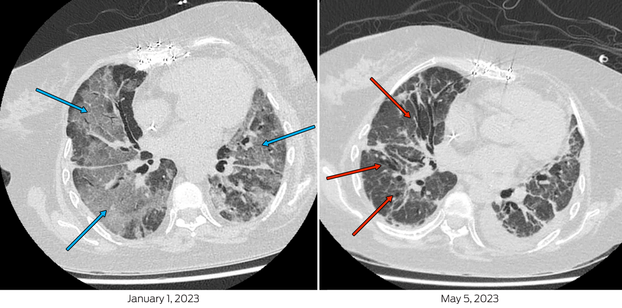

Her first severe acute respiratory syndrome coronavirus 2 (SARS‐CoV‐2) infection was diagnosed on 14 December 2022 and she was treated with molnupiravir for five days. On Day 11 of illness, she presented to hospital in respiratory distress with hypoxia (SpO2; 73% on room air). SARS‐CoV‐2 RNA was detected by polymerase chain reaction (PCR) with a cycle threshold of 21.8 (cobas SARS‐CoV‐2 and Influenza A/B, Roche). A chest computed tomography scan demonstrated extensive bilateral ground‐glass opacification (Box 1). She required intensive care unit admission for high‐flow nasal oxygen (FiO2 60%, flow rate 50 litres) and received tocilizumab, ten days of remdesivir, increased prednisolone, and piperacillin–tazobactam. Three days of pulsed methylprednisolone was prescribed for possible transplant rejection. Despite clinical improvement, SARS‐CoV‐2 RNA remained detectable with a cycle threshold of 16.2 (VIASURE SARS‐CoV‐2, flu and RSV, Certest Biotec) and SARS‐CoV‐2 was isolated from a cell culture.1 Whole genome sequencing identified Omicron BR.2 (variant of concern B.1.1.529) lineage, with molnupiravir‐associated mutational signatures,2 (sequence available on GISAID [Global Initiative of Sharing All Influenza Data]; 26/12/22: hCoV‐19/Australia/NSW_ICPMR_40135/2022 and 03/03/23: hCoV‐19/Australia/NSW_ICPMR_43136/2023).

Box 1 – Chest computed tomography scan on admission (left) demonstrates extensive bilateral ground glass changes, particularly in mid‐zones and perihilar regions (blue arrows), concerning for infection. Scan pre‐de‐isolation (right), with extensive interstitial and traction bronchiectatic changes (red arrows) indicative of fibrosis as opposed to ongoing infection